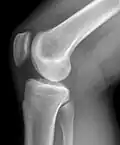

Самым доступным, одним из информативных и распространённых исследований является рентгенологическое исследование.

Стандартные проекции, применяемые при рентгенографии коленного сустава — прямая (передне-задняя) и боковая. По мере необходимости их дополняют правой или левой косой, а также аксиальной проекциями. Основным правилом при рентгенологическом исследовании коленного сустава является полипозиционность[2][3].

На рентгенограммах между суставными поверхностями костей видна так называемая рентгеновская суставная щель. Рентгеновской она называется потому, что, будучи заполненной хрящом и прослойкой синовиальной жидкости, которые не дают изображения на рентгенограммах, она имеет вид более прозрачной полосы между суставными поверхностями.

Рентгенограмма коленного сустава в боковой проекции. -